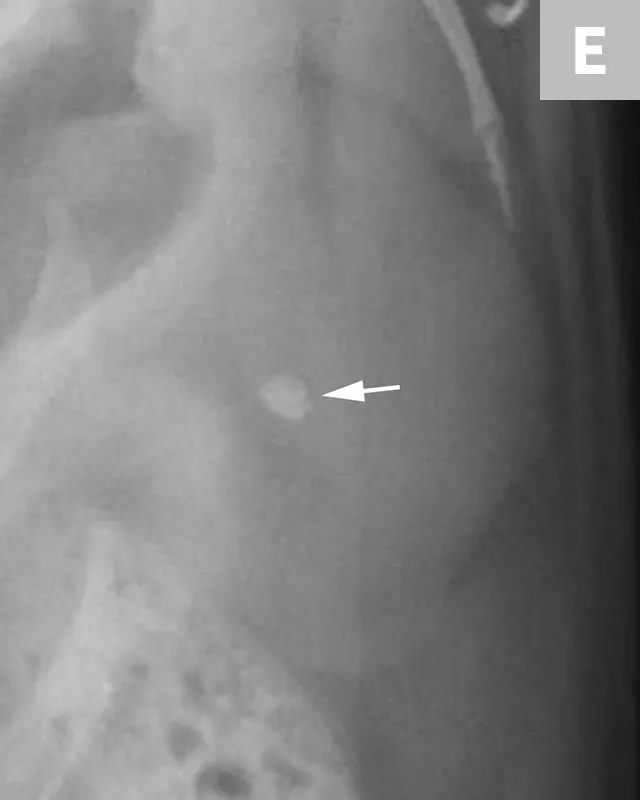

FIGURE 11A

Lateral radiograph of a male dog collimated to include the urinary bladder and os penis. Note the well-defined mineral opacity just proximal to and at the same level as the base of the os penis—a separate center of ossification (arrow). Also note the two soft tissue opaque nodules summating with the prepuce, presumed to be small nipples (arrowheads).

A separate center of ossification associated with the os penis may mimic a urethral calculus (Figure 11 A and B). A separate center of ossification can be seen at either end of the os penis and will be in line with the os penis. A calculus within the penile urethra would be seen ventral to the os penis in the location of the urethra. Contrast urethrography can be a helpful way to differentiate between a separate center of ossification and urethral calculus (Figure 11C).